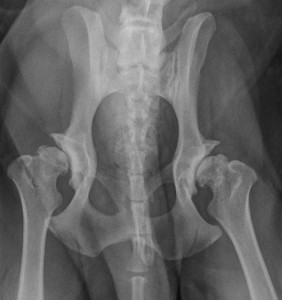

Le diagnostic est souvent clinique, mais la radiographie permet de confirmer et d’estimer l’importance des lésions.

La plus connue de ces malformations est la “dysplasie de la hanche” et il est reconnu que cette malformation a une forte composante héréditaire.

Un dépistage est donc préconisé, grâce à des radiographies qui peuvent se faire vers l’âge d’un an en moyenne (l’âge de dépistage dépend de la race, il convient de se renseigner auprès du club de race concerné).

Ces radiographies ont un double intérêt : elles permettent non seulement d’éliminer de la reproduction les animaux atteints, mais également de prendre, si l’animal est diagnostiqué dysplasique, les mesures nécessaires pour prévenir l’apparition rapide d’arthrose.